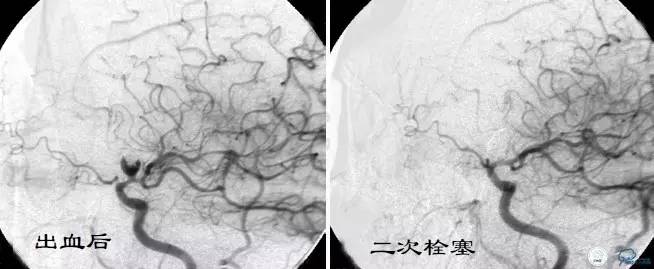

Case4 左ICA床突旁动脉瘤栓塞术后出血